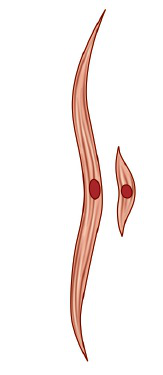

子宫复旧指的是生产结束后,子宫开始恢复到怀孕前的状态,一般要到产后 42 天才能完全恢复。过程中主要涉及到子宫肌肉纤维收缩力的恢复[1-3]。

图A. 子宫肌纤维在子宫复旧过程中由长变短